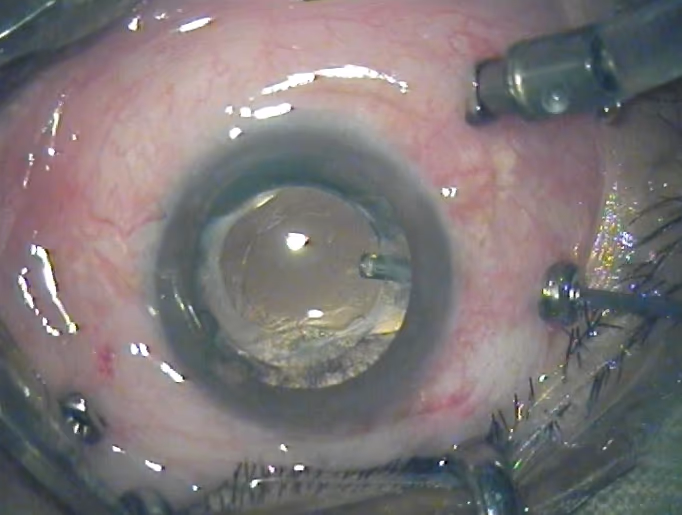

Este guia explica tudo o que você precisa saber sobre a cirurgia de membrana epirretiniana (MER): quando ela é indicada, como decidir se é o caminho certo para você, o que acontece durante o procedimento e como é a recuperação. Também abordamos taxas de sucesso, possíveis riscos e sinais de alerta no pós-operatório, para que você tenha informações práticas e claras para tomar uma decisão informada sobre a sua saúde visual.